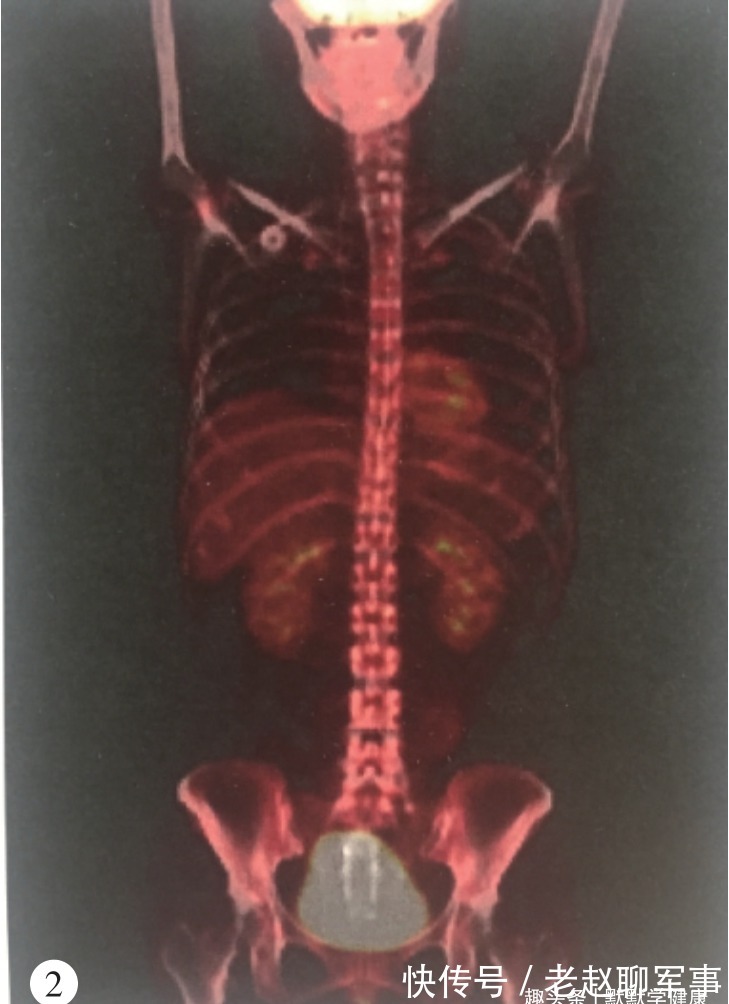

(2014年5月PET-CT结果)

2014年5月20日,开始吉西他滨+顺铂方案一线化疗并联合乐启生培本消癌IV方治疗,2个周期后PET-CT检查提示肝内病灶消失,颈部及腹腔淋巴结缩小,疗效评价部分缓解。看到这一结果,王兰的心情也逐渐明朗起来,“就像在黑暗中突然看到了一丝亮光”王兰回忆道。